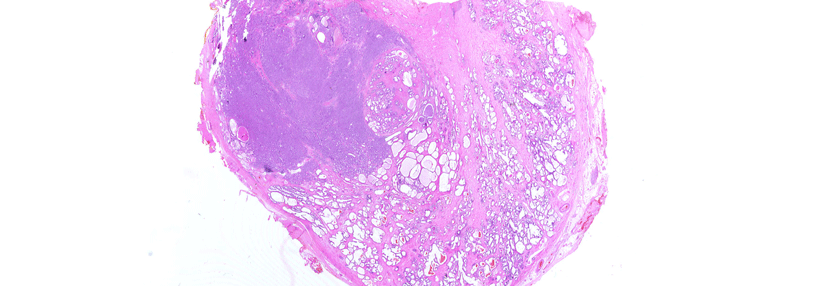

Prostatakrebs: Mit neuer Technik zu mehr Gewissheit

Besteht Verdacht auf ein Prostatakarzinom, muss das verdächtige Tumorgewebe genauer untersucht werden. Standard ist eine Gewebeentnahme mit einer…